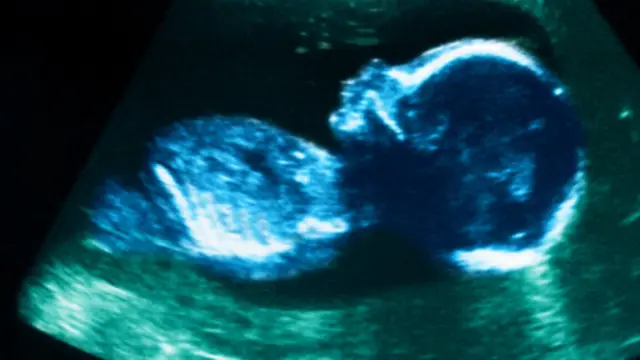

انتقد خبراء براءة اختراع أمريكي منح لقاعدة بيانات تستخدم اختبارات الحمض النووي "دي إن ايه" لإبلاغ الأزواج بالصفات التي يمكن أن ترثها ذريتهم في المستقبل.

وتقول شركة "23 آند ام إي" إن برنامجها " فاميلي تريتس انهيريتنس كالكيوليتور" (لتحديد الصفات الوراثية للمواليد مستقبلا)، يمكنه التنبؤ بمخاطر وراثة أمراض محددة وكذلك تفاصيل مثل الطول والوزن ولون العينين بل حتى الشخصية.

ويرسل الأزواج للشركة عينة من اللعاب لمعرفة الصفات التي سيكون عليها أطفالهم مستقبلا.